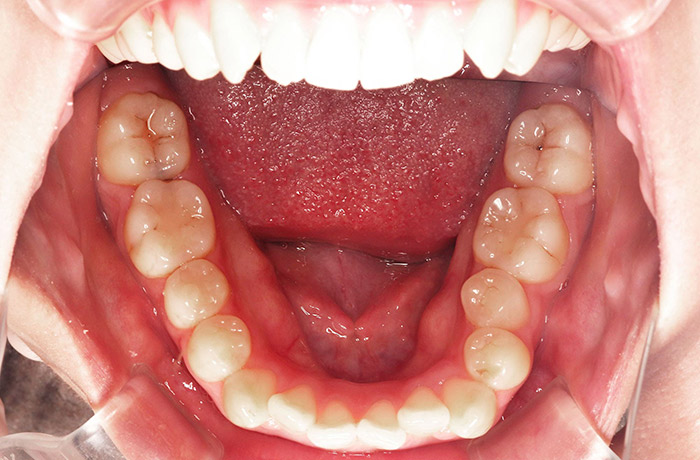

治療前

before

患者の症状 叢生、正中のずれ、上顎左右側切歯の口蓋側転位(交叉咬合)

治療方法 非抜歯で、マウスピース型カスタムメイド矯正歯科装置(インビザライン)による矯正

歯列弓を拡大することで非抜歯を可能にしました。

治療結果 側切歯の交叉咬合は解消、上下正中のずれも改善し咬み合わせが良くなりました。